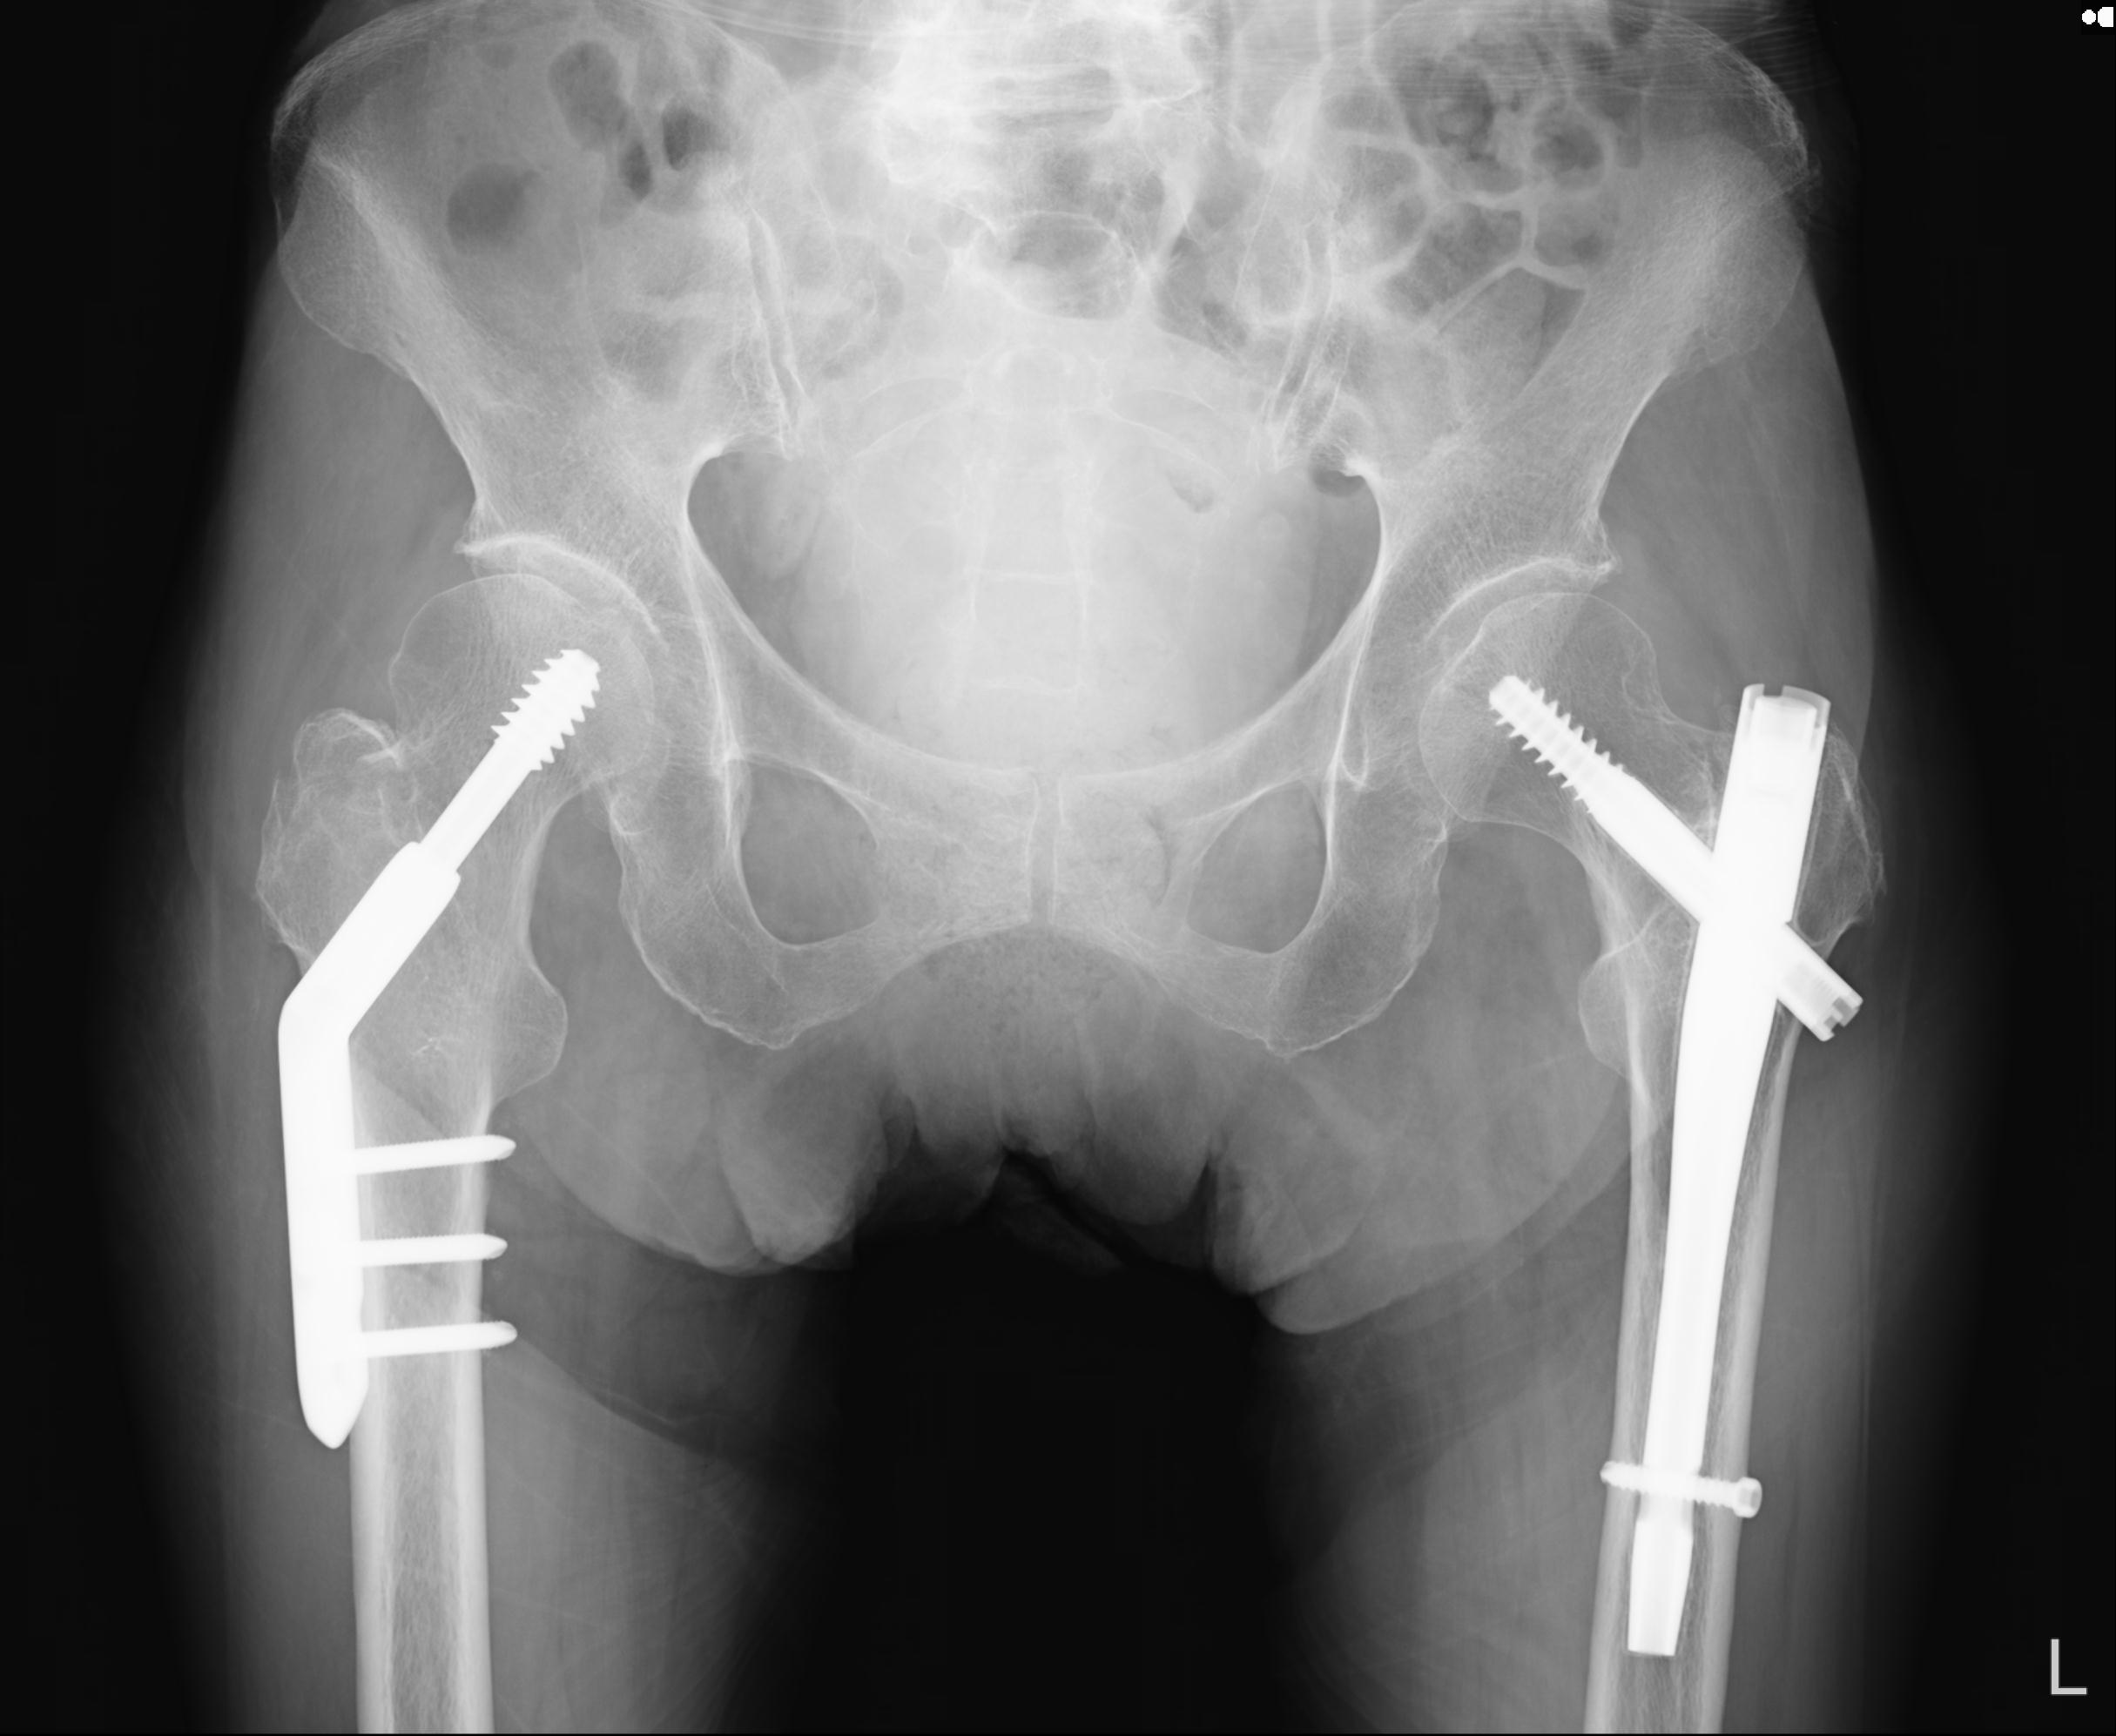

100703 1/27 両股正面+軸 1/29 両股正面+軸 94歳女性 パンソンロン

46666 1/28 両股正面+軸と 1/26 右手関節 2R 76歳女性 右転子部骨折

37 1/18 両股正面+軸 1/22 2R 86歳女性 右転子下